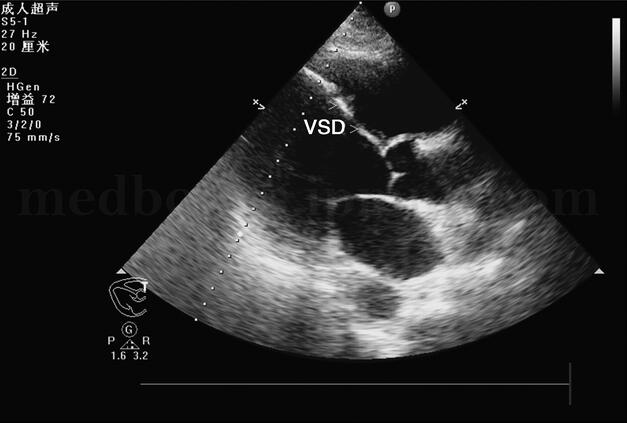

胸部X线片(图003‐1)示:肺水肿并双下肺感染改变;心尖部钙化,不除外室壁瘤可能;双侧胸腔积液,右侧叶间积液;右上肺高密度影。生化结果:心肌酶、肝肾功能正常。D‐二聚体:3129μg/L(0~300)。心电图(图003‐2)示:窦性心动过速,右束支传导阻滞,陈旧性前壁心肌梗死。超声心动图(图003‐3~图003‐5)显示室间隔破裂穿孔(因血栓封堵,无分流):室间隔中间可见两处回声缺失,直径均约为0.4cm,其左室面血栓形成。彩色多普勒:未见明确过隔分流。左室腔中间‐心尖段可见两块不规则形中低密度团块影附着,团块部分相互连接,两团块大小分别为5.4cm×2.95cm、6.1cm×1.23cm。

图003‐5 超声心动图3